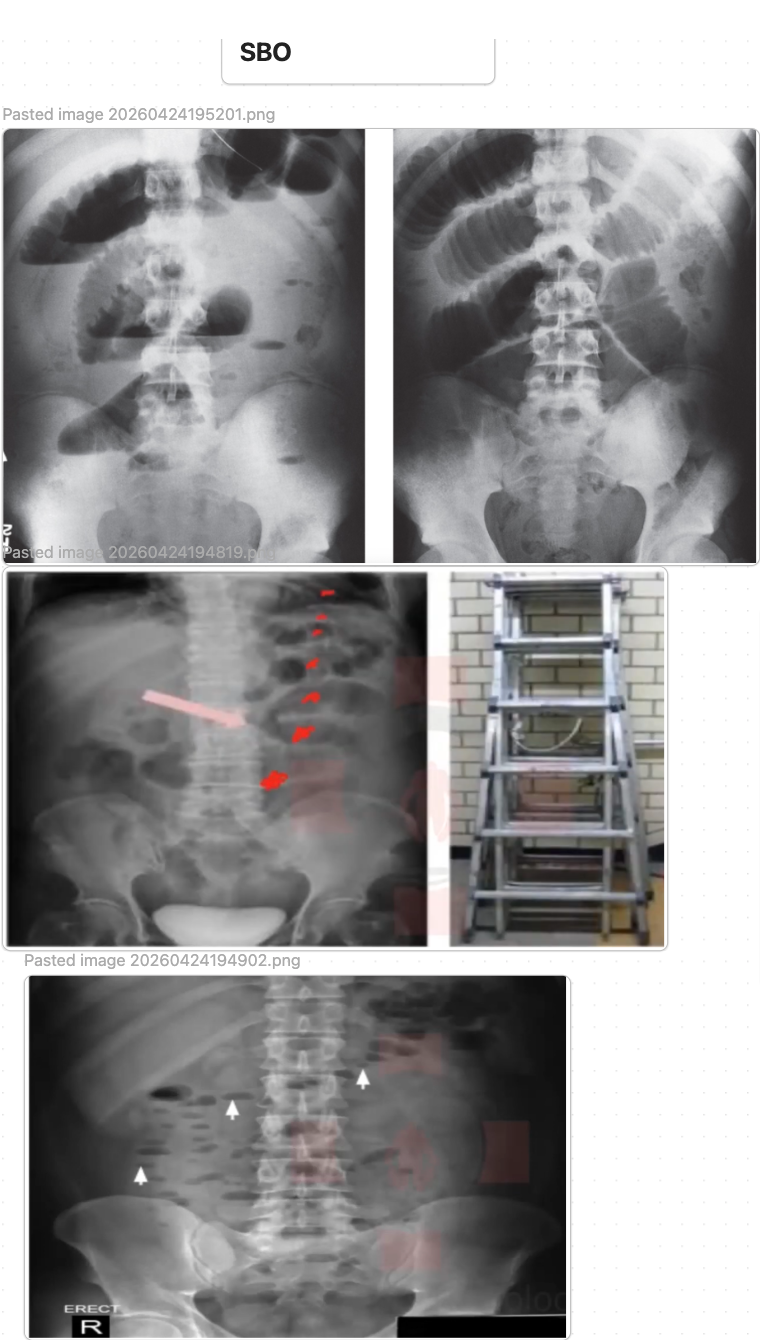

Small Bowel Obstruction (SBO)

• initial DATA: CBC, CMP/BMP, Mg/Phos, lactate; KUB may show dilated central small-bowel loops (>3 cm) with air-fluid levels and little distal colonic/rectal gas. CT A/P w contrast is usually obtained if SBO suspected and may show dilated small-bowel loops to a transition point with air-fluid levels and possible complications such as ischemia or closed-loop obstruction.